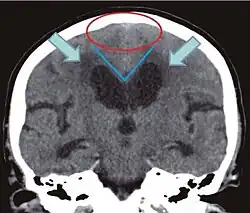

Hinweise auf einen Normaldruckhydrozephalus sind:

- disproportionale Erweiterung der äußeren Liquorräume(DESH--„disproportionately enlarged subarachnoid space hydrocephalus“): Weitstellung von Subarachnoidalräumen an lateraler Konvexität, besonders der Sylvischen Fissur und Engstellung der parasagittalen Subarachnoidalräume der oberen Konvexität und der medialen Hirnoberfläche[29]

- Corpus-Callosum-Winkel < 90°[27] / typischerweise 50–80°[30] im koronaren Schnitt[27] senkrecht zur Ac-pc-Ebene[31] auf Höhe der hinteren Kommissur[27]